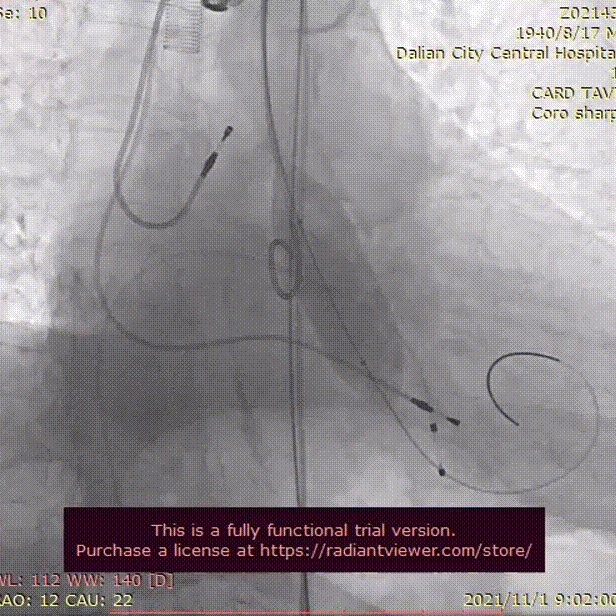

术中影像

LCA造影

RCA造影

主动脉根部造影

22mm球囊充分扩张

瓣膜初始定位, 选择0位释放

TaurusElite AV26mm瓣膜,瓣上2mm 工作位造影

瓣膜形态良好 位置理想